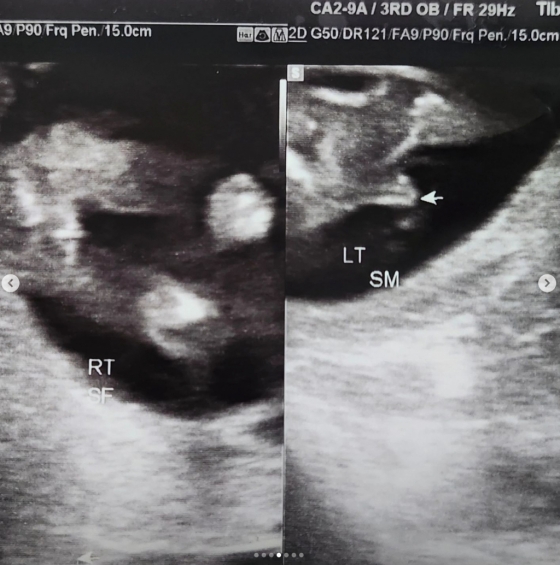

정인영은 26일 초음파 사진을 올리며 "정말 감사하게도 왕자님과 공주님을 함께 만나게 됐다"라고 밝히고 "나이 마흔에 다태아. 이것만으로도 저는 이미 고위험 산모지만 아직까지는 씩씩하게, 또 매일매일 즐겁게 잘 지내고 있다"라고 전했다.

사진은 처음 확인한 1센티 미만의 아기집, 임테기 노예시절, 임신확인 후 제일먼저 구입했던 용띠 쌍둥이 양말, 성별 확인 초음파(꺄아 화살표 넘 부끄) 없는 솜씨로 열심히 꾸미는 초음파앨범, 어플이 예측해준 아가들의 모습...